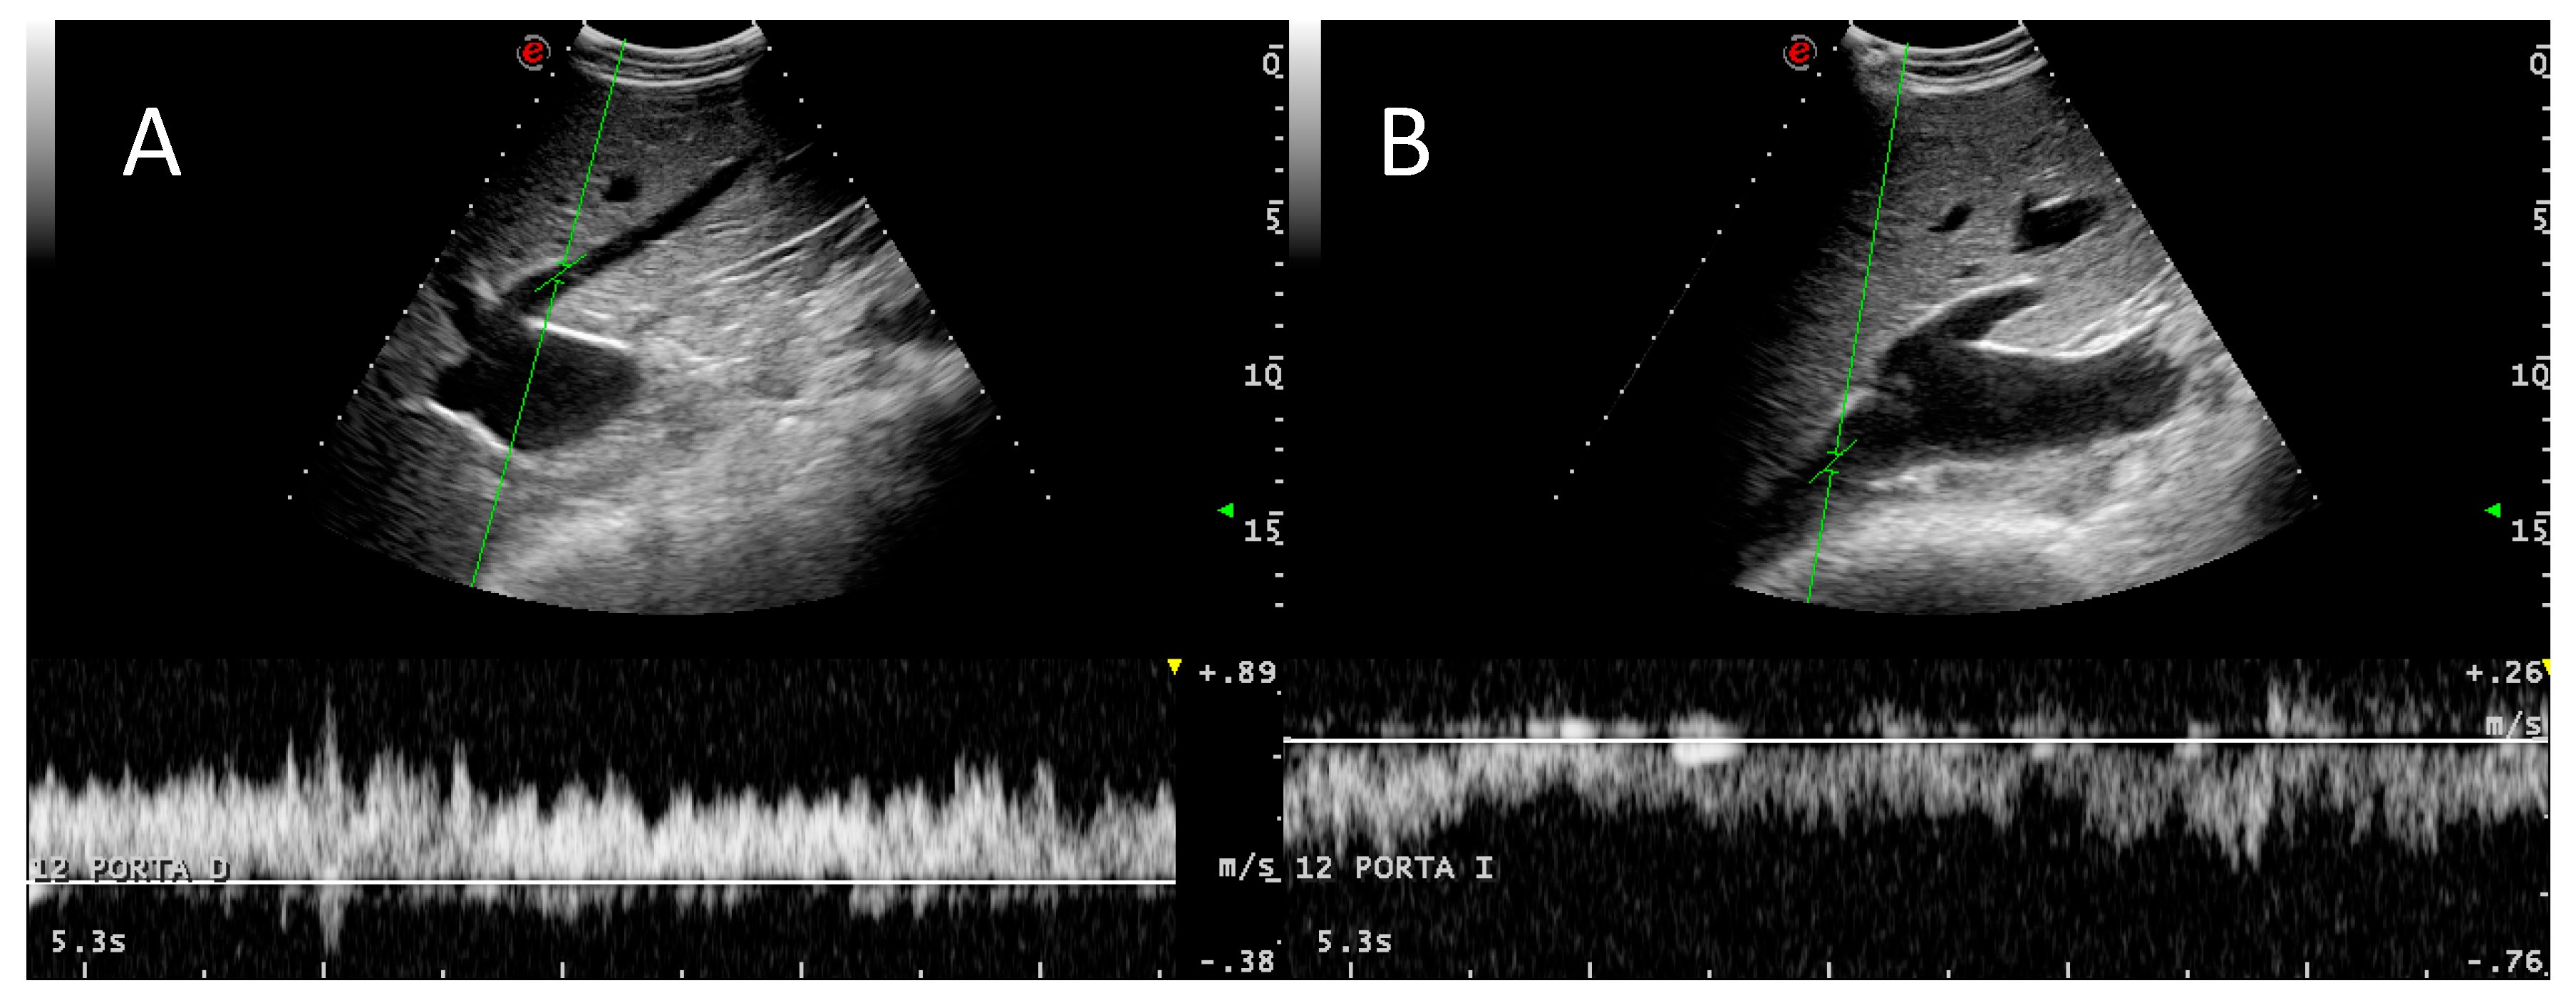

3.2. Portal System